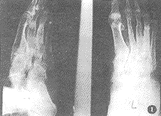

2.1 X线表现(图1~3):

图1 左足跗骨及第二、三、骨弥漫性骨质破坏,骨干粗细不均匀,跗骨间关节亦受侵犯。软组织肿胀

, http://www.100md.com

图2 右足跗骨骨质破坏,并可见骨质硬化

图3 右足软组织肿胀,第三、四骨近端骨质破坏,骨皮质凹凸不平

2.1.1 软组织弥漫肿胀占100%。其中8例见软组织有稍高密度结节影(均为临床软组织呈结节性肿胀者)。

2.1.2 软组织内见低密度之窦道影。

2.1.3 足骨改变:无骨质改变者11例,单纯骨皮质侵蚀14例,皮质、髓质破坏者75例,有死骨形成者5例。骨增生硬化改变48例,骨干增粗畸形者40例,骨膜反应18例,单骨破坏者26例,多骨破坏者65例。

3.3 X线表现:①软组织肿胀,在重点显示软组织的X线片上可见稍高密度类似生姜样的结节状改变(病理为霉菌性肉芽肿形成);②骨破坏是由周围软组织感染直接蔓延而来,故骨破坏的次序是先皮质后髓腔,可有皮质局限性破坏,皮质、髓腔广泛溶骨性破坏等表现形式。③死骨少见,④足骨间关节及多骨受累为其特征。⑤病程长的病例可见骨增生硬化及骨干增粗等骨修复表现。作者认为该病与一般慢性骨髓炎有相似改变,但骨破坏始终呈进行性,与骨修复相比,骨破坏始终占优势,该点也被病理检查所证实。